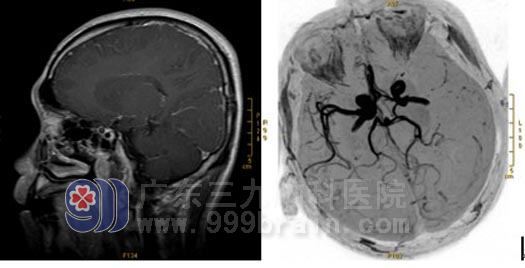

磁共振检查所见:

▲左大脑中动脉供血区(左侧额颞叶及左侧基底节区)大片梗塞灶,双侧丘脑小片状梗塞灶,MRA检查示左侧大脑中动脉闭塞。